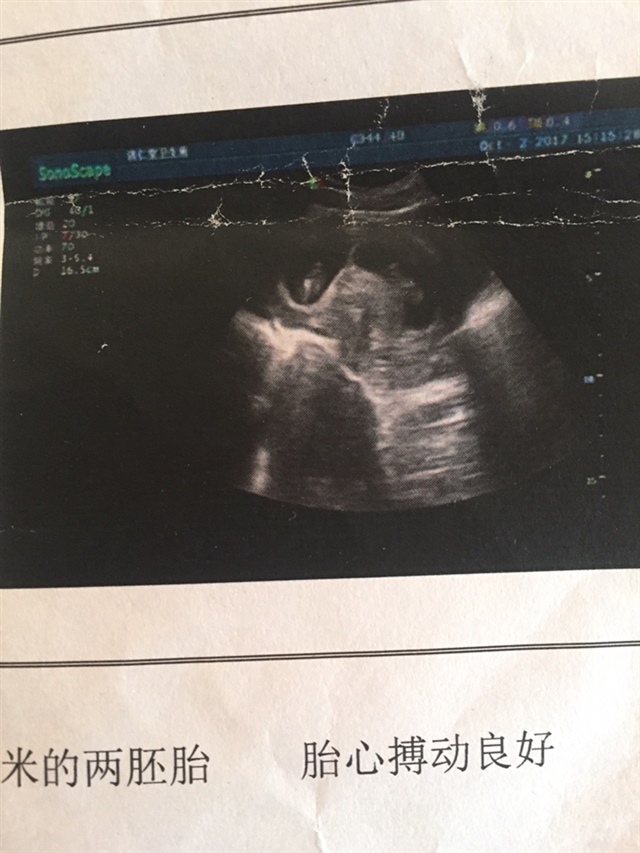

可乐双胞胎兄弟

2018-06-01

2736 人回复